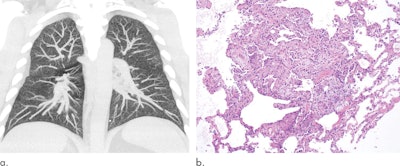

Maximum intensity projections of the CT data of a 32-year-old man with a history of vaping show diffuse centrilobular nodularity (a). Histologic sections of the patient's transbronchial cryobiopsy show a micronodular pattern of airway-centered organizing pneumonia that corresponds to the centrilobular nodularity seen on CT (b). All images courtesy of the RSNA.When recognized early, most EVALI patients improve with vaping cessation and glucocorticoid treatment, the authors noted. However, recent longitudinal analysis of EVALI cases showed that vaping can induce pulmonary inflammation and subsequently lead to severe pulmonary scarring and chronic dysfunction in surviving patients.

The researchers found that the most common radiologic findings associated with EVALI thus far have been organizing pneumonia and diffuse alveolar damage, followed by diffuse alveolar hemorrhage and acute eosinophilic pneumonia, all of which they previously explored in depth during a special interest session at RSNA 2019. Other imaging patterns mentioned in reports include hypersensitivity pneumonitis, exogenous lipoid pneumonia, and giant cell interstitial pneumonia, though the group recommended that these less-common patterns not be qualified as signs of EVALI just yet.